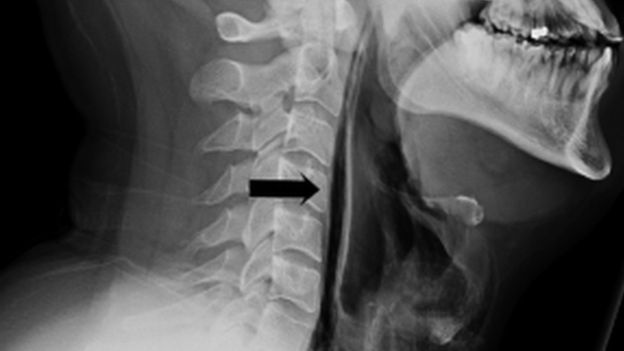

السهم الأسود يشير إلى خطوط الهواء(باللون الأسود) في منطقة الأنسجة الرخوة

وأظهر فحص بالأشعة أن الهواء هرب من قصبته الهوائية، إلى الأنسجة الرخوة من العنق، عبر التمزق.